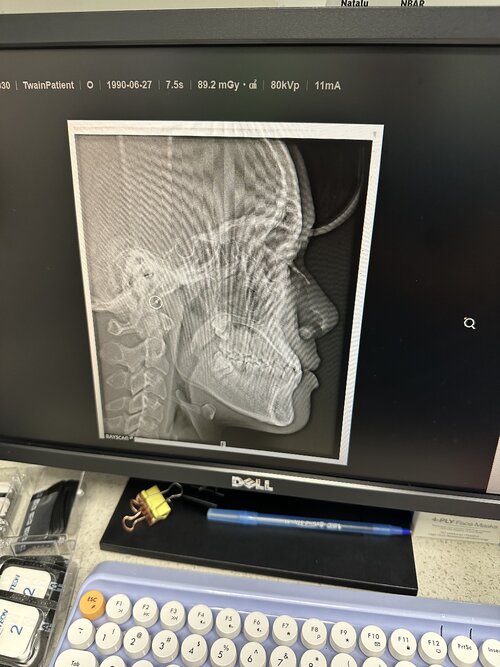

Im currently 18 yr old asian male, I have an underbite, and below I’ve attached images of some of the x-rays taken. My orthodontic surgeon is suggesting to pull teeth, but I know that’s utter nonsense and will recess me like crazy. I tried to bring up the possibility of a maxillary deficiency rather than a mandibular one, but he argued that my lower jaw was protruding and that my maxilla was fine. He said moving my upper jaw forward would give me an unnatural look, which I don’t really believe all that much. May the good people of org advise me on my situation? I’m thinking I should just save up for lefort later on. I also have all my wisdom teeth still even though I should probably get them extracted (at least the bottom ones). Would getting my wisdom teeth extracted help my underbite?